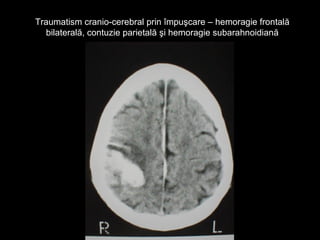

Traumatism cranio-cerebral prin împuşcare – hemoragie frontalăTraumatism cranio-cerebral prin împuşcare – hemoragie frontală

bilaterală, contuzie parietală şi hemoragie subarahnoidianăbilaterală, contuzie parietală şi hemoragie subarahnoidiană

Traumatism cranio-cerebral prinîmpuşcare – hemoragie frontalăTraumatism cranio-cerebral prin împuşcare – hemoragie frontală bilaterală, contuzie parietală şi hemoragie subarahnoidianăbilaterală, contuzie parietală şi hemoragie subarahnoidiană